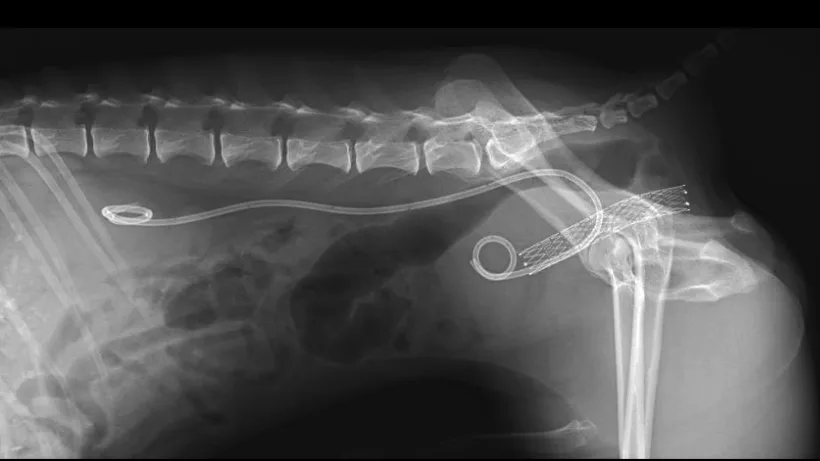

4、尿路閉塞が起こっている場合

・尿道閉塞:尿道ステント設置術、膀胱瘻チューブ設置術

・尿管閉塞:尿管ステント設置術、SUBシステム設置術

・尿道&尿管閉塞:上記の手術を併用、尿路移設術 ± 膀胱尿道全摘出術